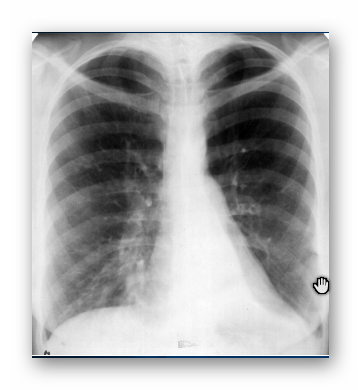

OBRZĘK PŁUC

RTG